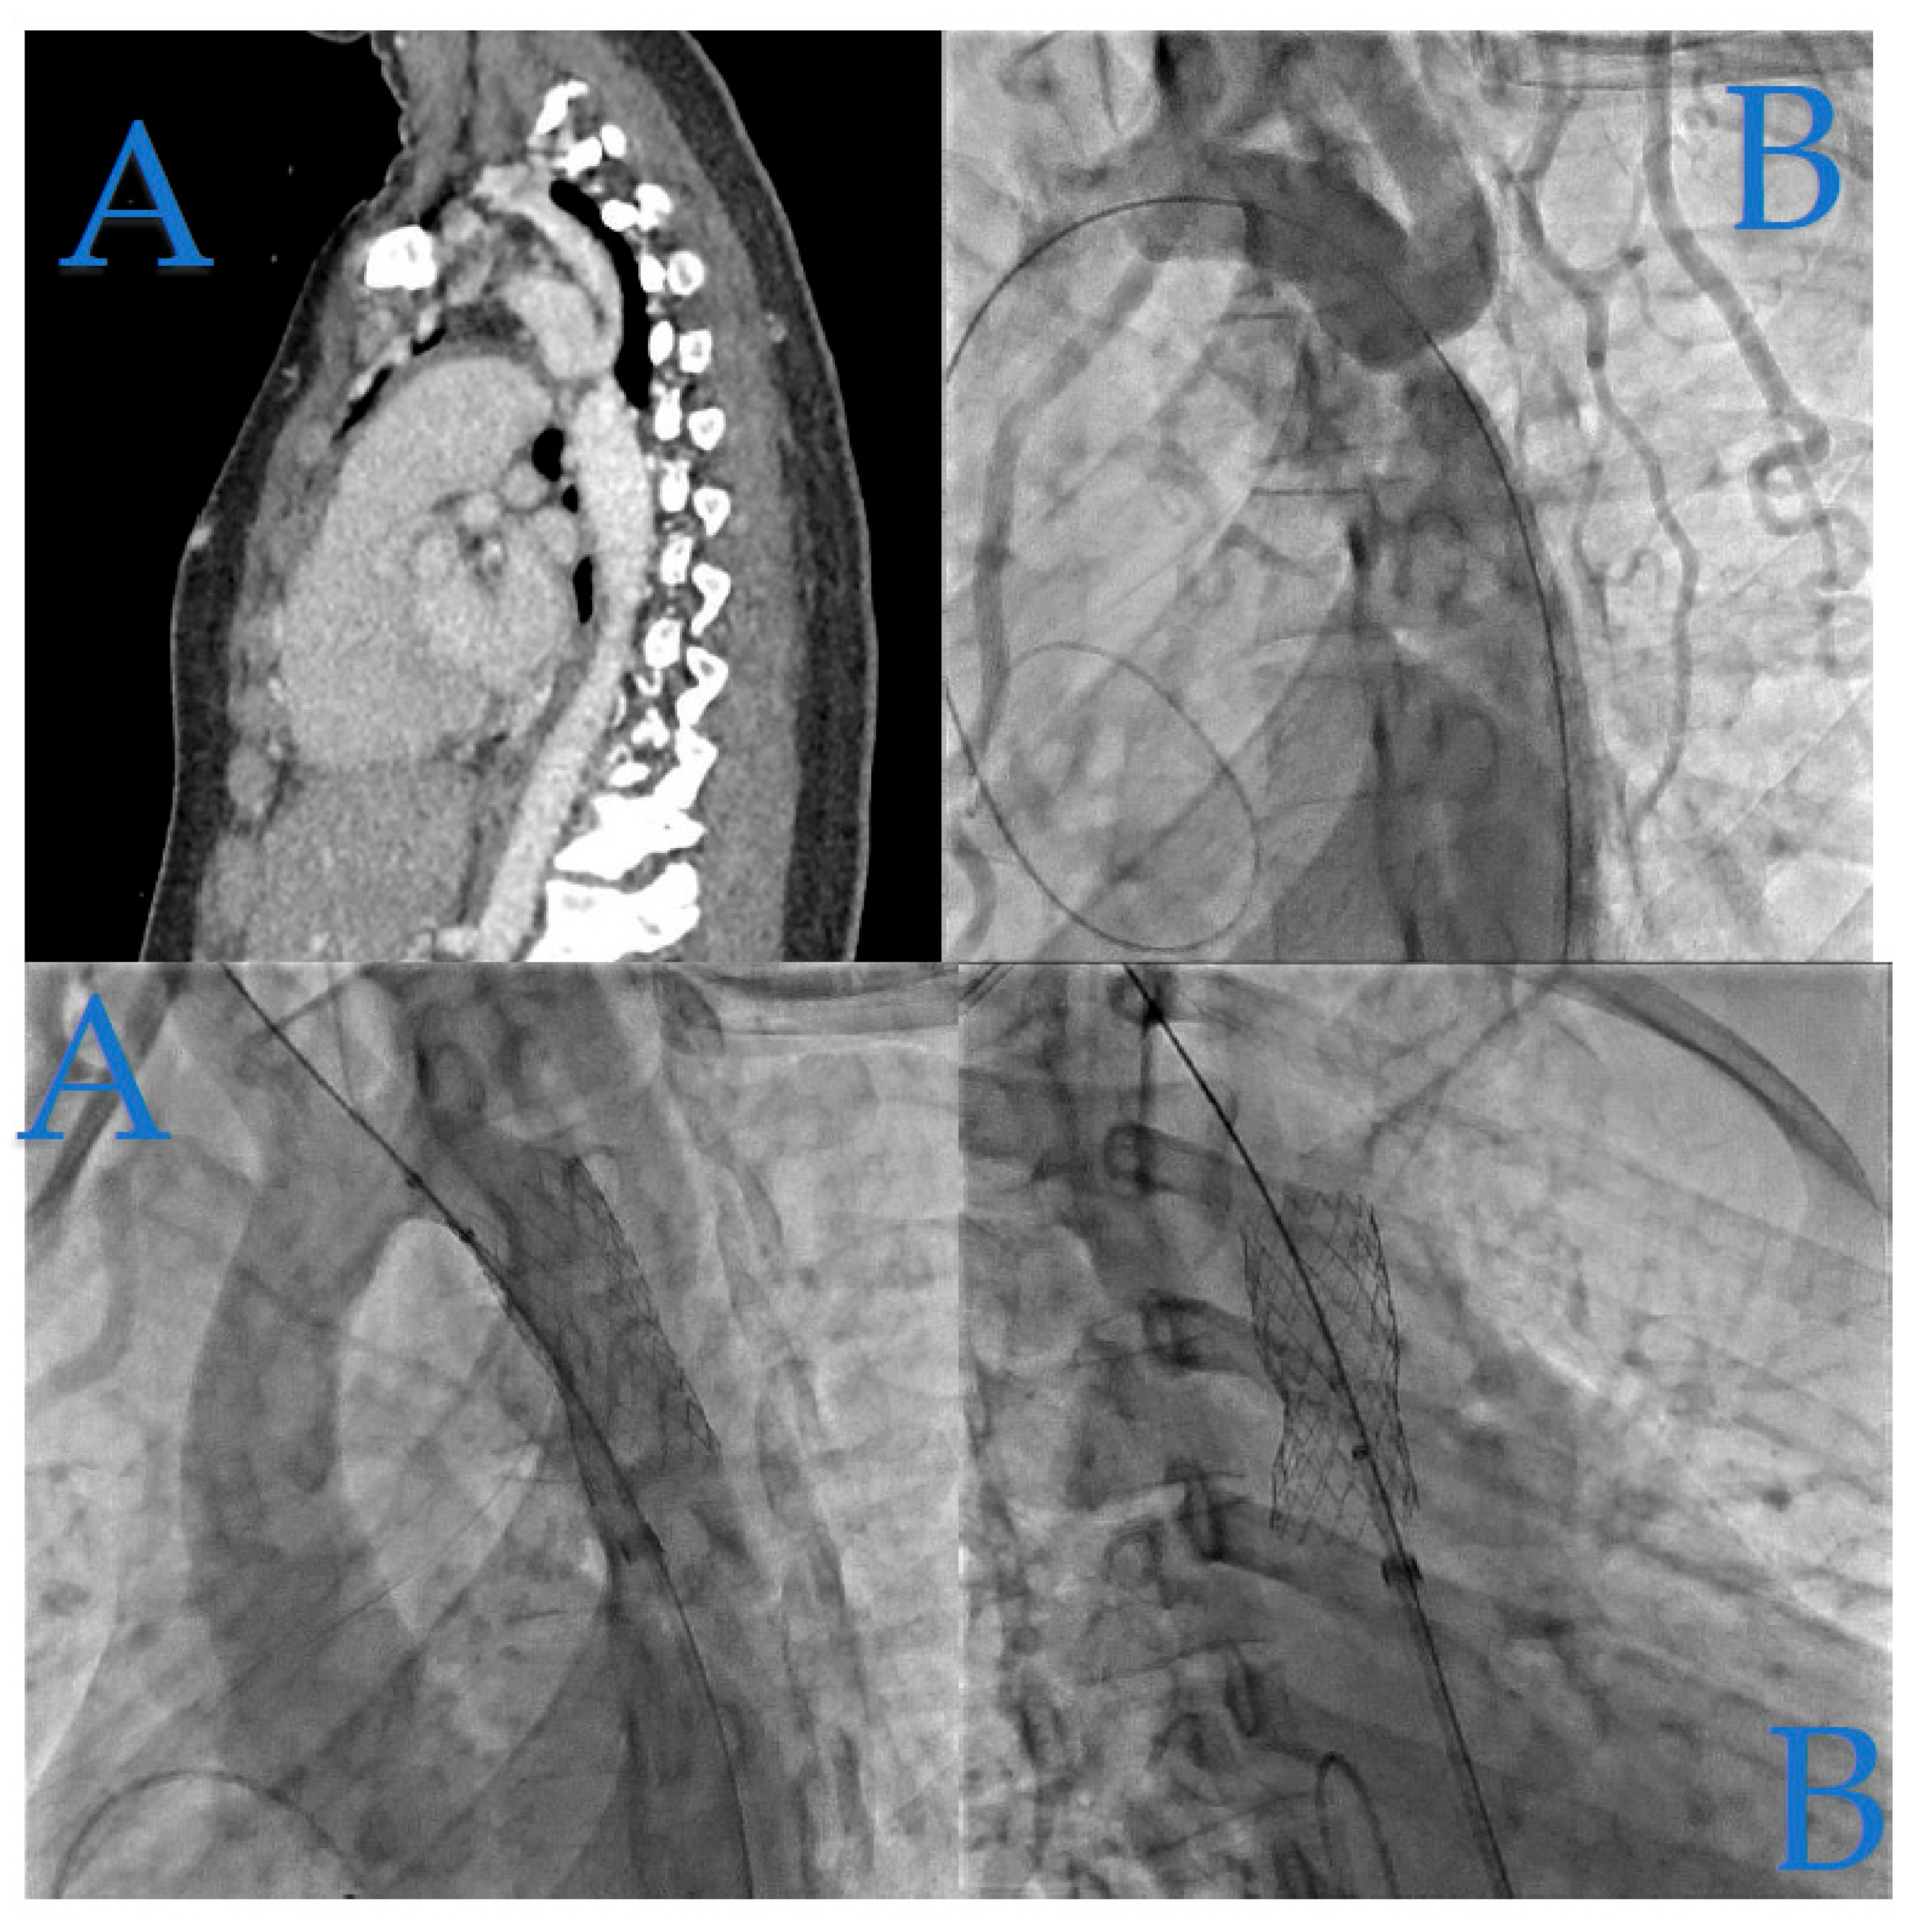

In Figure 2, we present the case of a 4-month-old infant weighing 5.8 kg, who underwent coarctation correction surgery using an extended end-to-end anastomosis at just 2 weeks of age. However, at 4 months, the patient developed hypertension (HTA) and a significant blood pressure gradient of 40 mmHg, indicating recoarctation.

Figure 2. Infant Coarctation Case. (A): The CT scan highlights the recoarctation, precisely measuring it at 2 mm. (B): Angiography further confirms the recoarctation, showing a trans-coarctation gradient of 40 mmHg. (C): Following diagnosis, angiography after a 5.5 mm non-compliant Boston balloon dilatation revealed excellent hemodynamic results, resulting in a residual gradient of only 16 mmHg, as seen in the angiographic images.